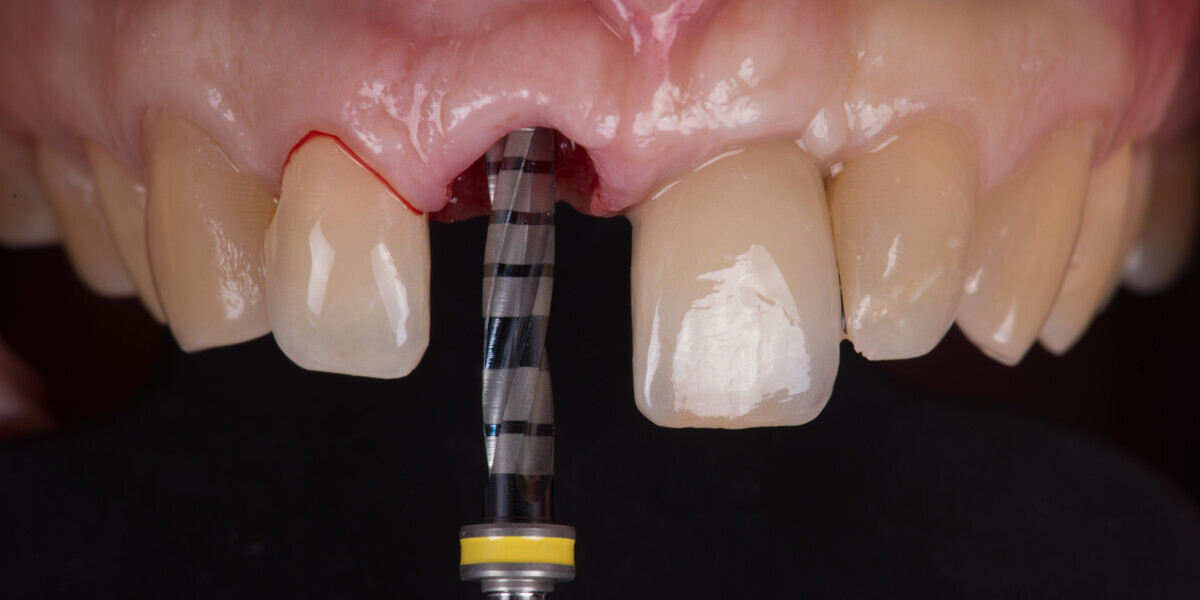

Immediate placement and restoration of a Straumann BLX implant replacing maxillary incisors